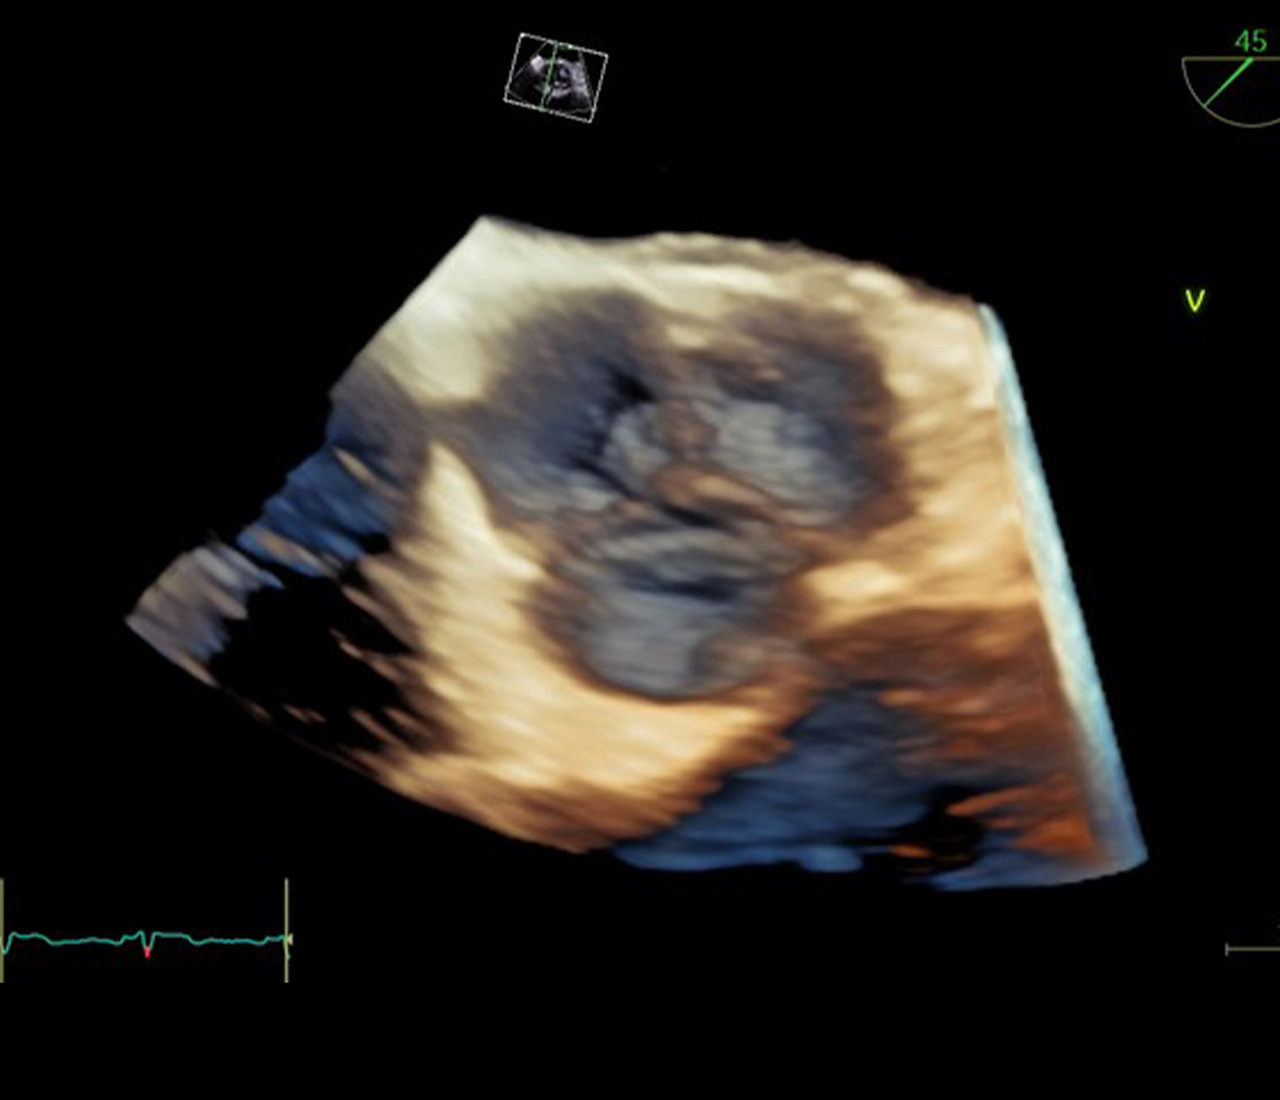

新たな診断の世界

UlPath(ウルパス)は「超音波を学びたい人」に開かれた、オンライン学習プラットフォームです。超音波技術の基礎から専門的な応用まで、段階的な学習プロセスに応じたコンテンツや、超音波医学の専門家として必要な知識・技能の習得を目指すためのコンテンツなど広く収載していきます。